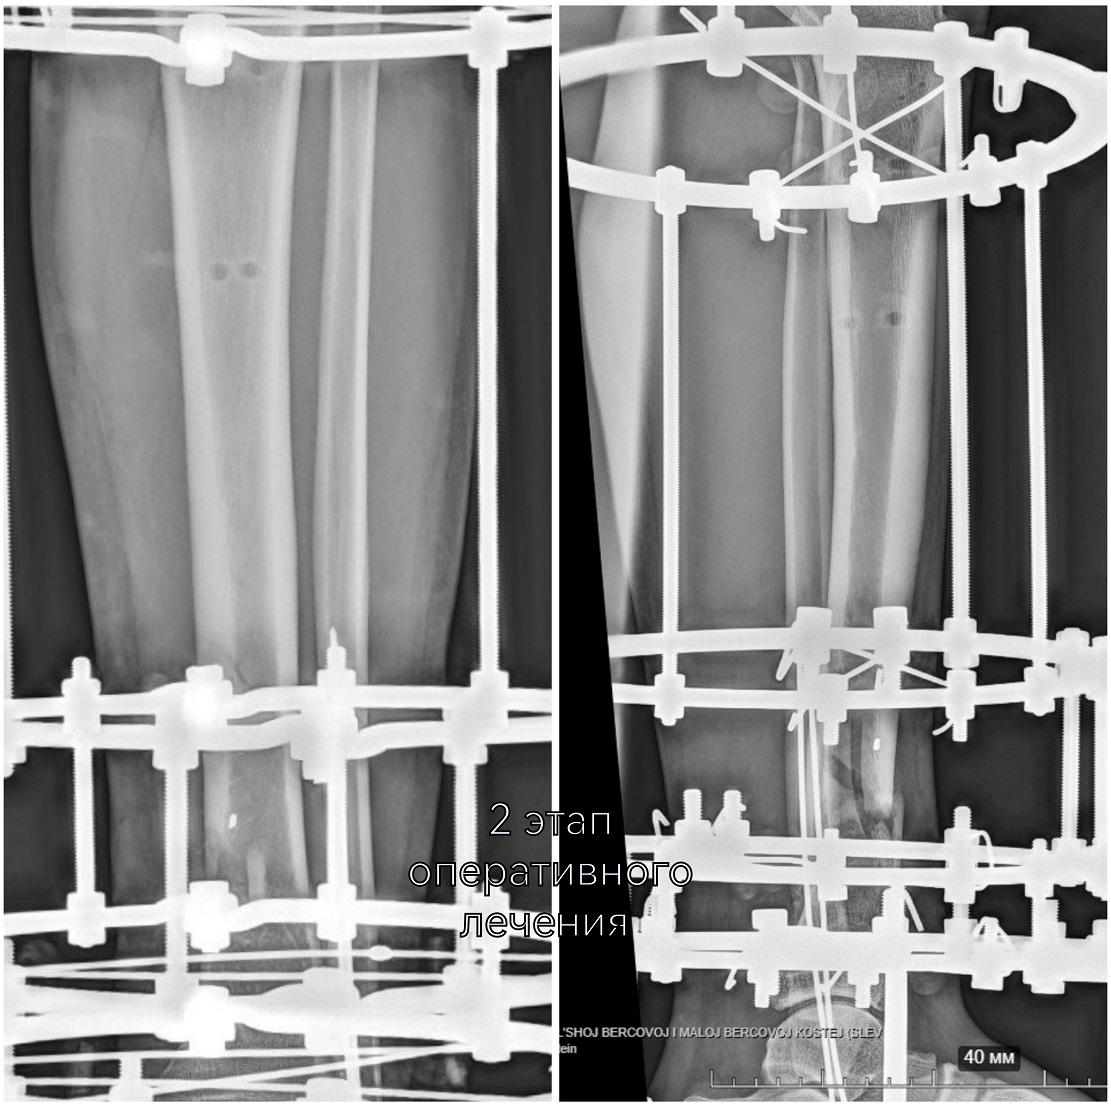

-На втором этапе первично установленный стержневой аппарат демонтирован и выполнен окончательный остеосинтез аппаратом Илизарова. На сегодняшний день это самый надежный и управляемый вариант. Данный вид фиксации позволяет проводить раннюю реабилитацию и передвигаться с нагрузкой на поврежденную ногу. Послеоперационный период проходит спокойно, мужчине назначено комплексное восстановительное лечение, включающее физиотерапевтические процедуры и занятия ЛФК, - объясняет лечащий врач Юрия, травматолог-ортопед Артём Мещеряков, выполнивший второе вмешательство.